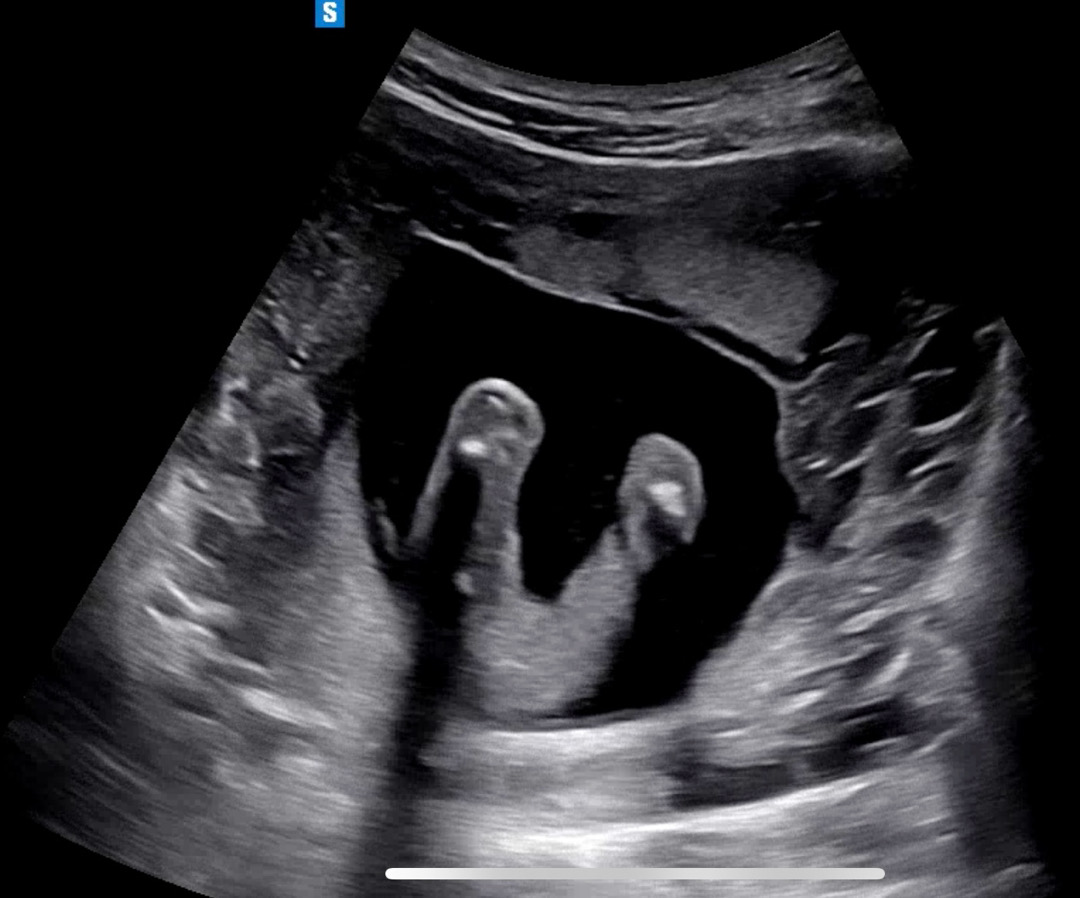

17주 1일이고 오늘 초음파때 성별 알려주실 줄 알았는데 씩씩하다는말밖에 해줄 수 없다고 하시더라고요? 그래서 아들인가 싶었는데 초음파 영상 아무리 봐도 다리사이에 뭐가 안보이는거 같아서 저는 딸 같은데 딸일까요? 아들일까요?